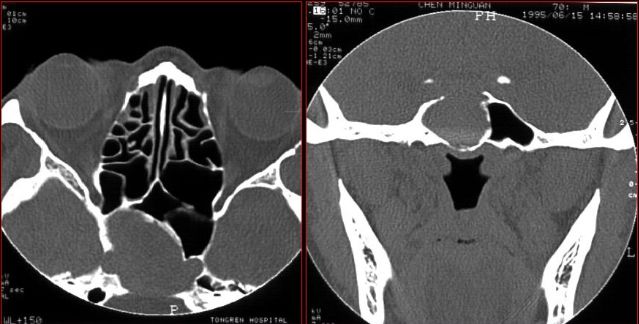

蝶窦炎—眶尖综合症

鼻窦炎—眶尖综合症